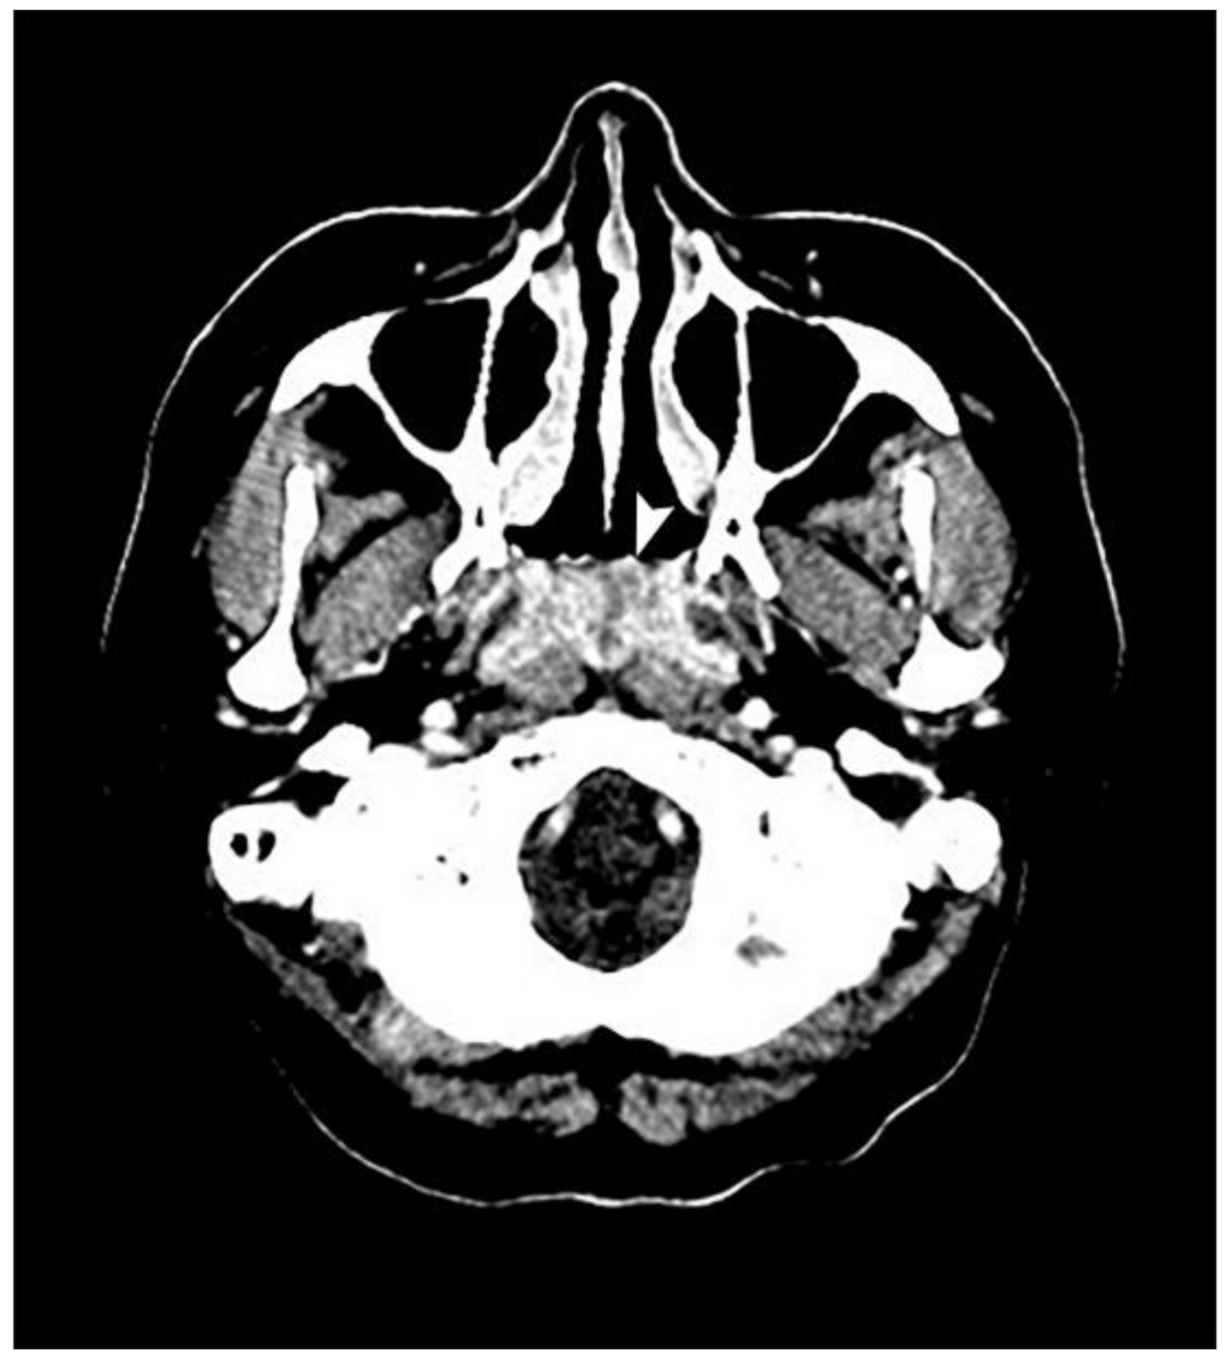

2. Case Presentation